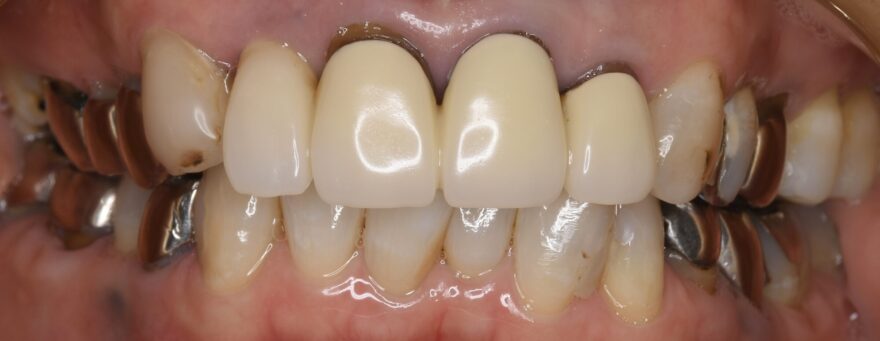

治療後の口腔内写真

白く輝く美しい歯が入りました。

長期にわたる理想的な噛み合わせが付与されました。

こちらにも、何でも噛める機能的なセラミック歯が入りました。。

裏から見ても上の前歯のインプラントブリッジは自然な仕上がりです。

こちらも、どこにインプラントが入っているか分からない自然な形態を再現できました。